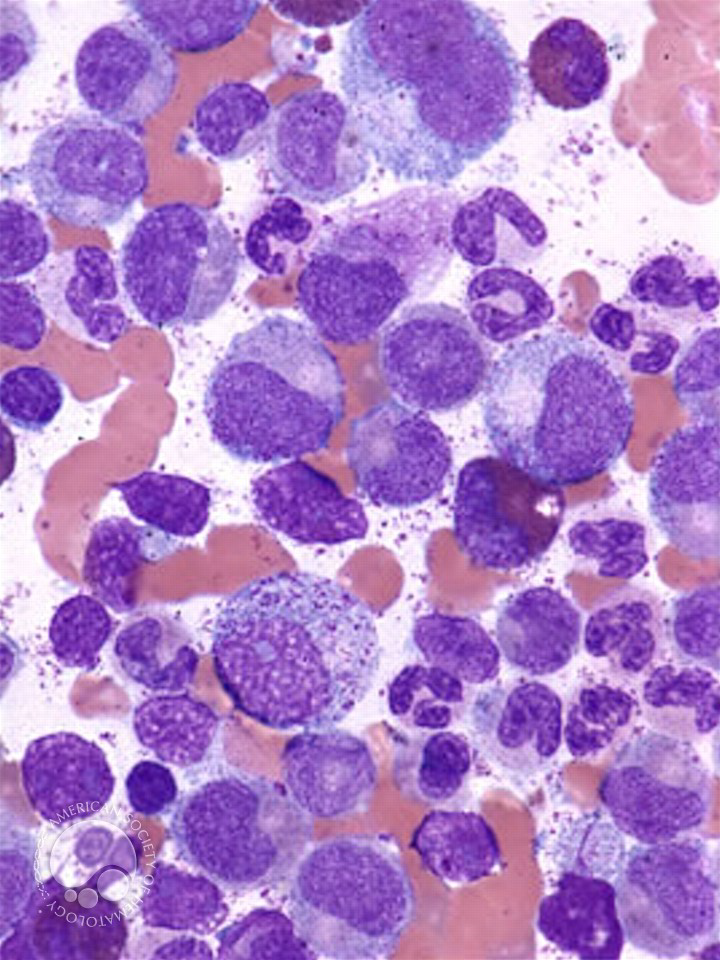

52 year old Female Presenting With Dyspnea And A Diagnosis Of